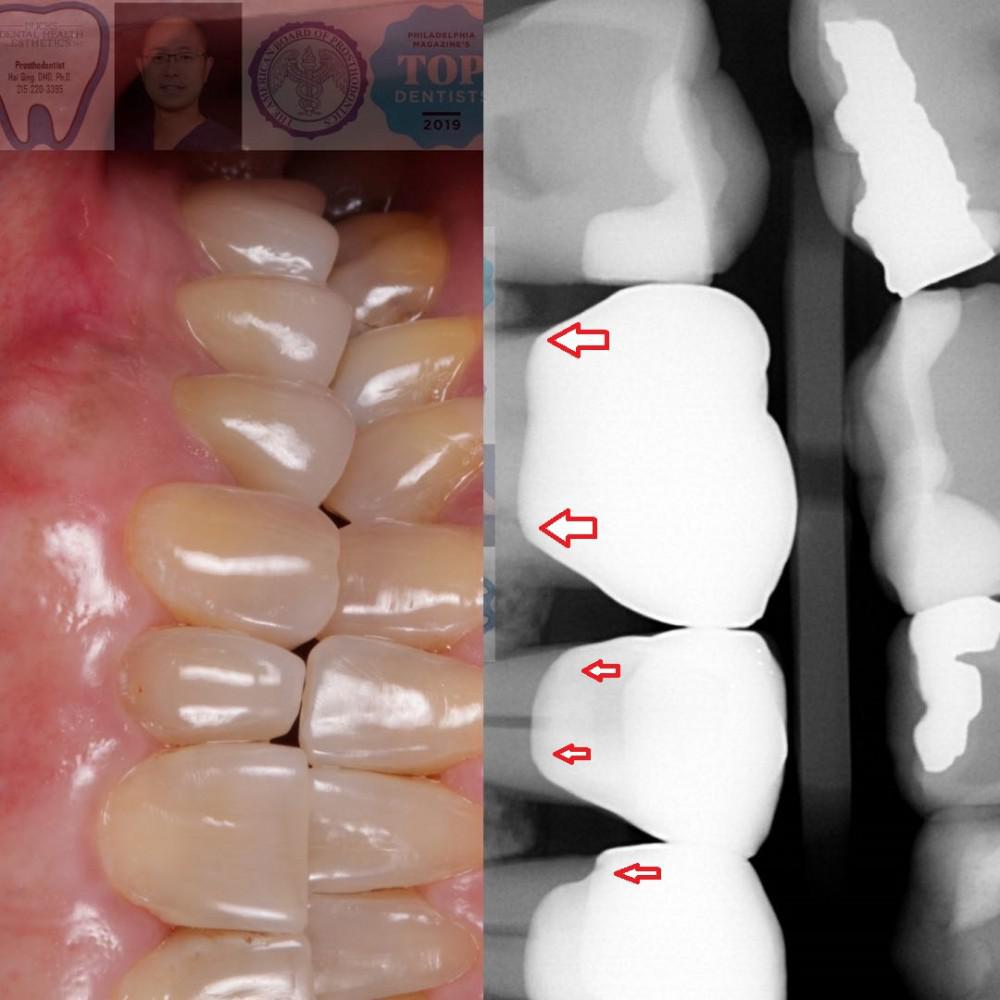

The crowns were then tried to make sure they meet all the Prosthodontics standards before delivery. One of the most important steps is to use a Bitewing Xray to check the marginal seal. ( arrows indicate the perfect seal, no bulky overhang or gap)